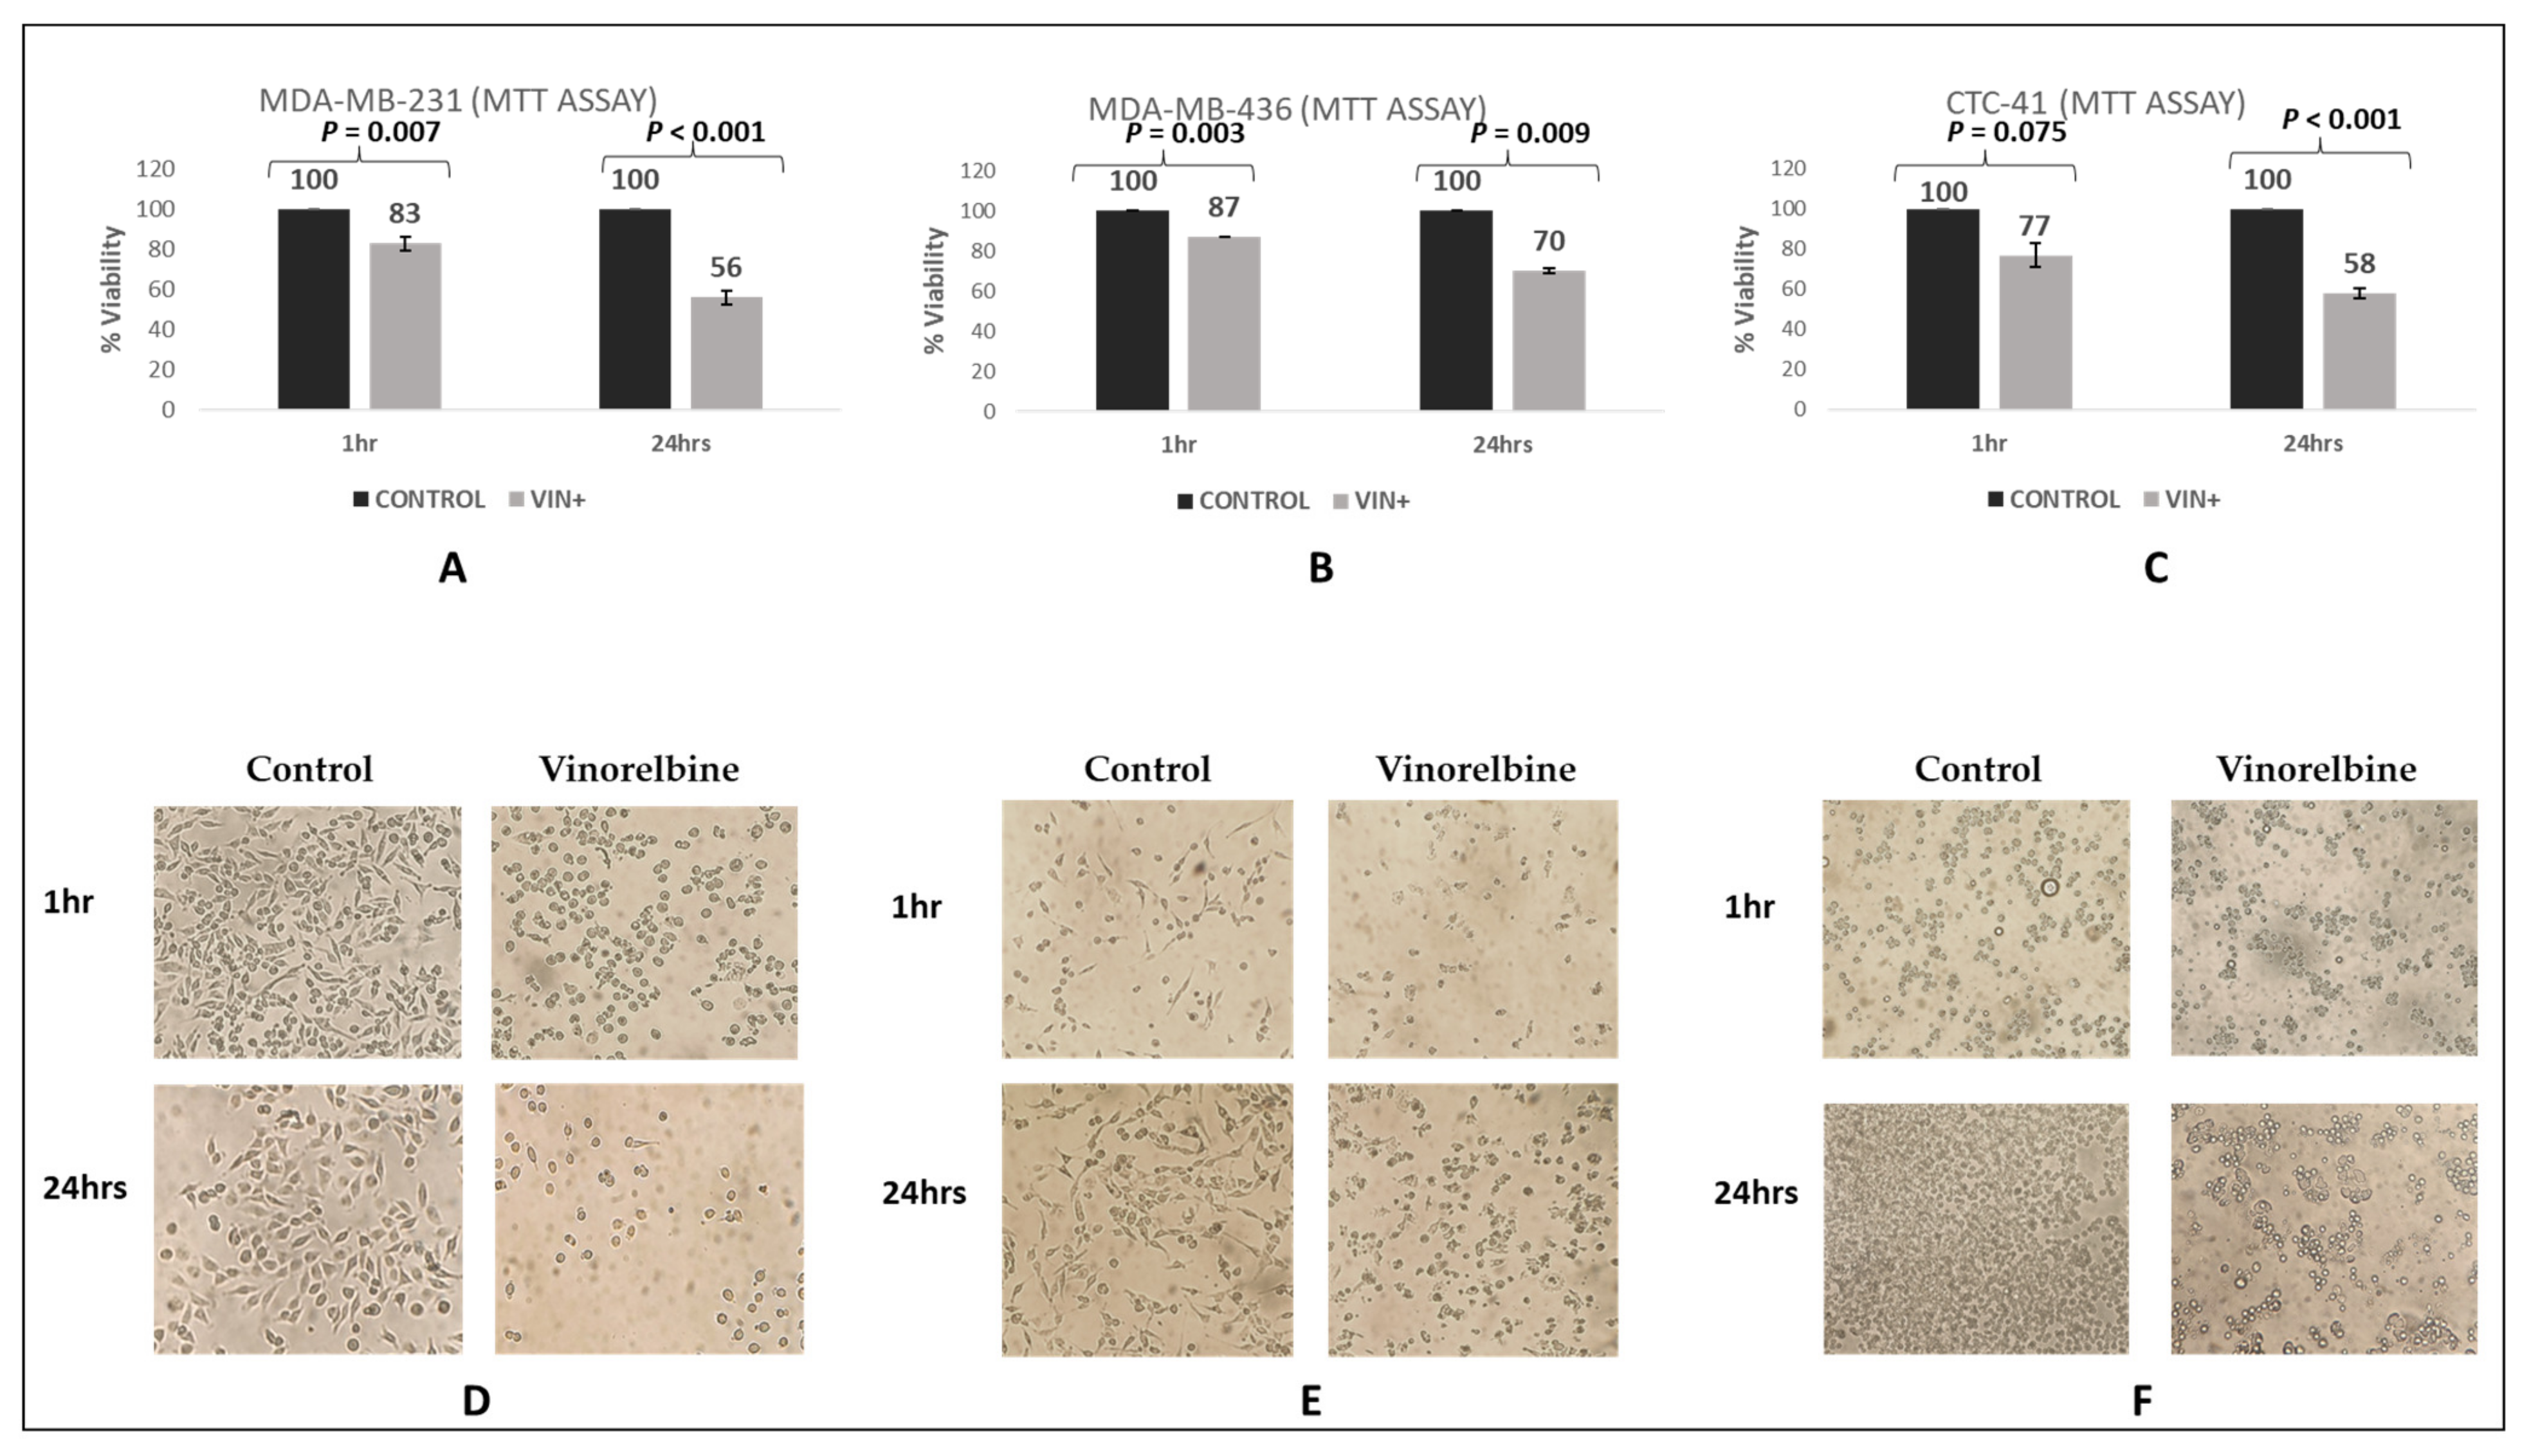

3.4. Control Experiments of Vinorelbine Effects in TNBC and in CTC-41 Cell Lines